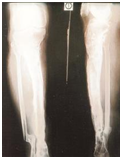

Figure 2: Case 2

1. Infected non union right lower tibia.

2. Radiograph of right tibia fibula with Ilizarov in situ (2nd Post-op).

3. Radiograph of right tibia fibula with Ilizarov in situ after 6 months follow up.

4. Final radiograph of tibia fibula after 8 months follow up.

5. Clinical appearance of the patient (Standing position).

6. Clinical appearance of the patient (sitting position).